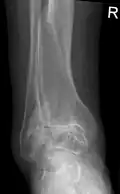

Lateral X-ray scan of ankle with secondary osteoarthritis

Lateral

Frontal X-ray scan of ankle with secondary osteoarthritis

Frontal

Secondary osteoarthritis of the ankle (due to an old bone fracture) in an 82-year-old woman